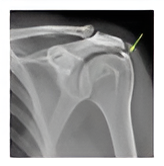

Calcific tendinitis

Calcific deposits in the tendon can result in acute severe pain. The diagnosis is made by x-rays and ultrasound scan. In early stages, ultrasound guided needling and aspiration is done. Severe pain, large lesions and chronic recurrent cases may need arthroscopic debridement.